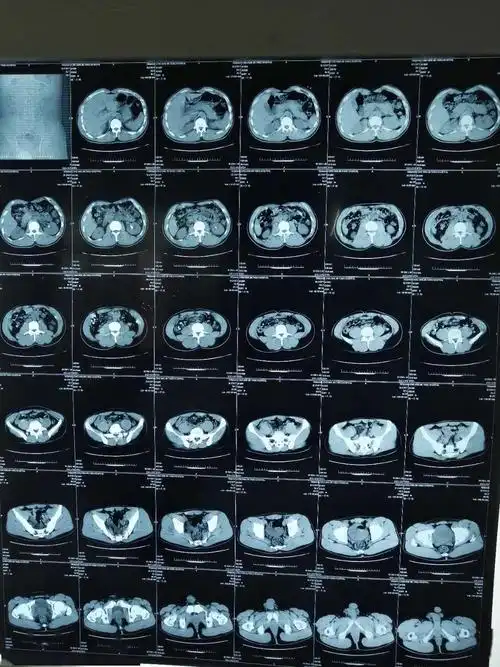

左肾结石彩超,ct检查情况2患者目前病情可考虑行经皮肾镜肾结石碎石

肾结石的硬度已经颠覆了医生的认知,肾结石的ct值了解一下

泌尿系统结石之肾结石ct表现